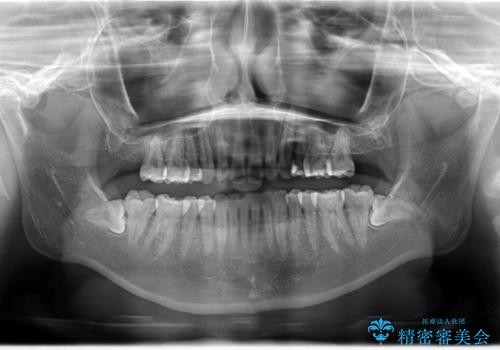

ハーフリンガル矯正 抜歯をして前歯を下げる

- 上顎の両側第1小臼歯抜歯による抜歯矯正を計画した。

上顎の抜歯により上の前歯の位置を大幅に後ろに下げることができます。

奥歯の位置関係など、様々な要素を加味し、適応を判断する必要があります。